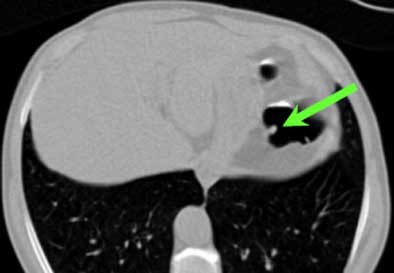

| Top to bottom: A 10-mm polyp in the splenic flexure can be seen in axial, sagittal, coronal, and 3D views. All images courtesy of Dr. Riccardo Iannaccone, University of Rome "La Sapienza." |

Per patient, virtual colonoscopy yielded an average sensitivity of 89.9% (95% CI, 90.9%-96%), average positive predictive value of 88% (95% CI, 83.3%-91.5%), and average negative predictive value of 93.5% (95% CI, 90.9%-96%), the authors wrote. In the more rigorous per-polyp analysis, VC's overall sensitivity was 64.4% (95% CI, 60.2%-68.7%; 72% for neoplastic polyps), including 95.5% sensitivity for polyps ≥ 8 mm (95% CI 92.1%-99%; 100% for neoplastic polyps), and 86% for polyps ≥ 6 mm (95% CI, 81.7%-90.5%).

Virtual colonoscopy produced 16, 16, and 21 false-positives for each of three readers, most due to the presence of thickened folds, and surprisingly in the prep-free study, few false-positives (4, 4, and 5, respectively) were due to fecal material. "This result is correlated to the fact that the use of an effective fecal tagging strategy in our study helped the readers in the differentiation between fecal material and colonic polyps," the authors wrote.

There were also 54, 57, and 52 false-negatives at VC, with no clear cause determined for 59, 51, and 53 of them, even in retrospective analysis. These may have been due to the limits of spatial resolution in the image data, but most of the lesions carried a very low likelihood of malignancy, the group noted. Interobserver agreement between the three readers was high both per-polyp (k = 0.61-0.64) and per patient (k = 0.79-0.91).